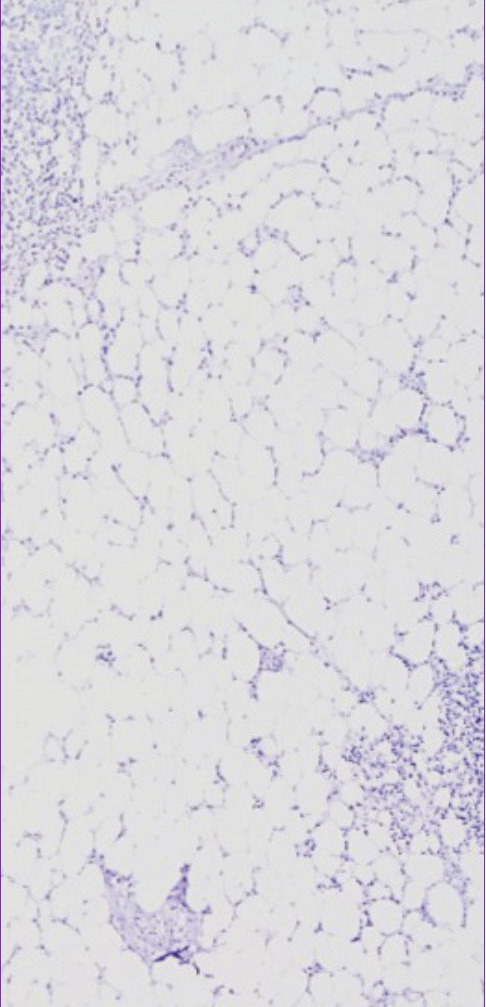

| 经六轮微波处理 |

样本:乳腺癌组织(FFPE) 使用苏木精和伊红染色后进行观察 | 经六轮VectaPlexTM处理 |

* 如上图所示,经多轮处理后,VectaPlexTM 可最大程度保留热敏感组织的形态